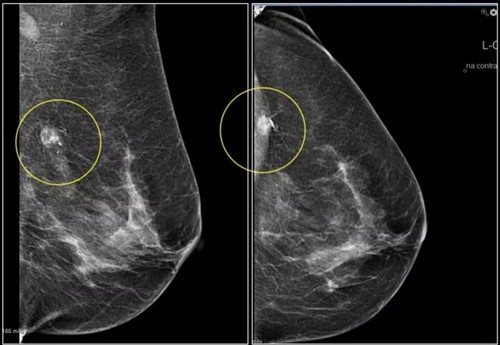

- Стромальные кальцинаты, откладывающиеся в соединительной ткани. Эти обызвествления обычно единичны. Их причиной считают атеросклеротические изменения в сосудах, фиброаденомы или опухоли жировой ткани (липомы). Эти образования чаще бесформенные или точечные (похожи на россыпь звезд на небе, крупы на столе). Реже они бывают овальными или напоминают зернышки попкорна.

- Протоковые, как видим из названия, локализуются в млечных путях (протоках). Их причиной считается застой молока и очень опасная патология — рак (при интрадуктальном раке протоки сужаются, и создается благоприятная среда для выпадения солей кальция). Соли кальция в протоке откладываются в форме иголочек, точек.

- Дольковые кальцинаты обнаруживаются в дольках железы и свидетельствуют о мастопатии, аденозе или патологическом течении возрастной инволюции бюста. Формой эти «камешки» похожи на полумесяц, кусочки яичной скорлупы либо чашу.

Обнаружив на снимке молочных желез наличие обызвествлений, врач-маммолог должен в первую очередь изучить их форму и локализацию. Это нужно для того, чтобы составить последующий план обследования пациентки. В случае подозрения на рак молочной железы, женщине назначают биопсию и гистологическое исследование.